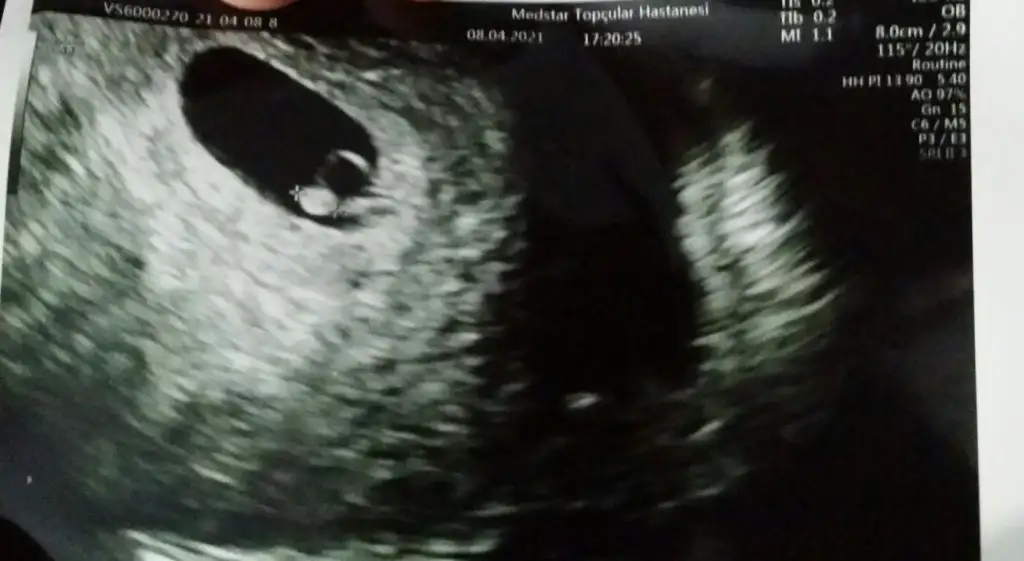

Cinsiyetini öğrendiniz miEki Görüntüle 2777702 Eki Görüntüle 2777703 Eki Görüntüle 2777704 6+4 7+4 11+4 yorumlayabilir misiniz? Henüz belli olmadı cinsiyetimiz

Ramzi teorisine göre cinsiyet tahmini yapacagim ilk ultrasyon resminizi atin bakiyim. Eger cinsiyetiniz belliyse hic söylemeeyin bakalm dogru tahmin edebilecekmiyim daha dogrusu ramzi teorisi hakli cikacak mi?